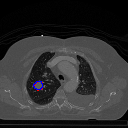

A qualitative analysis of our results reveals the strengths and weaknesses of our proposed model. In most cases, regardless of the size of the ground truth, our model predicts the tumor shapes very well. This is evident from Figure 4 where the ground truth and the prediction (by Deeply Supervised MultiResUNet) are shown in red and blue respectively. Although the tumors are in various arbitrary locations within the lung and appear in diverse sizes, the red and blue margins appear to coincide almost perfectly.

Figure 5 shows a comparison between predictions by the MultiResUNet model and Deeply supervised MultiResUNet model. It can be seen that the latter can delineate the tumor edges more accurately than the former. The ground truth (shown in red) and the prediction (shown in blue) have a more consistent alignment with each other in Deeply Supervised MultiResUNet’s prediction.